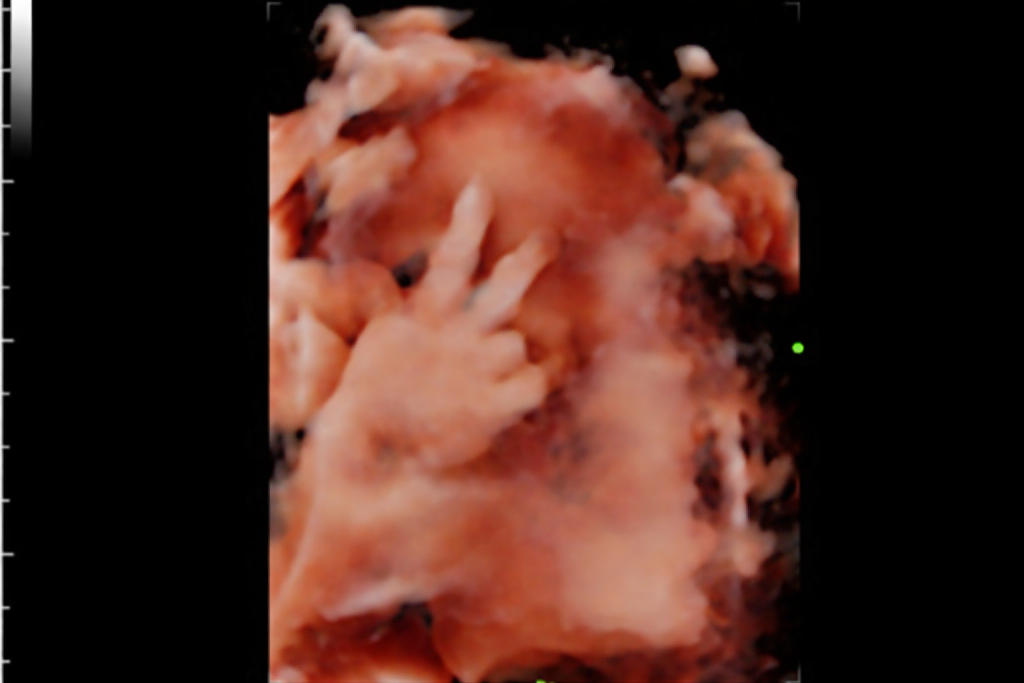

HD Live (5D) Scan: Unparalleled Clarity

HD Live, often known as 5D scanning, brings an almost magical touch to pregnancy imaging, turning ordinary ultrasounds into beautifully lifelike moments. With advanced lighting and shadowing, it creates soft, detailed images that resemble your baby’s first photograph—complete with tiny expressions and delicate features. Many parents are amazed to see their baby smile, yawn, or gently move, making the experience deeply emotional and unforgettable. It’s more than just a scan; it’s a chance to connect, imagine, and fall in love even before birth, capturing memories that families often cherish long after the pregnancy journey ends.